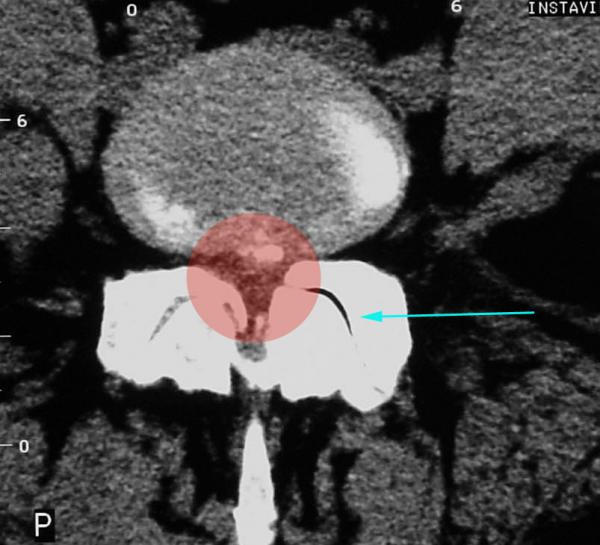

Als Behandlungsmaßnahmen kommen Facetteninfiltration bzw.Facettendenervation in Frage